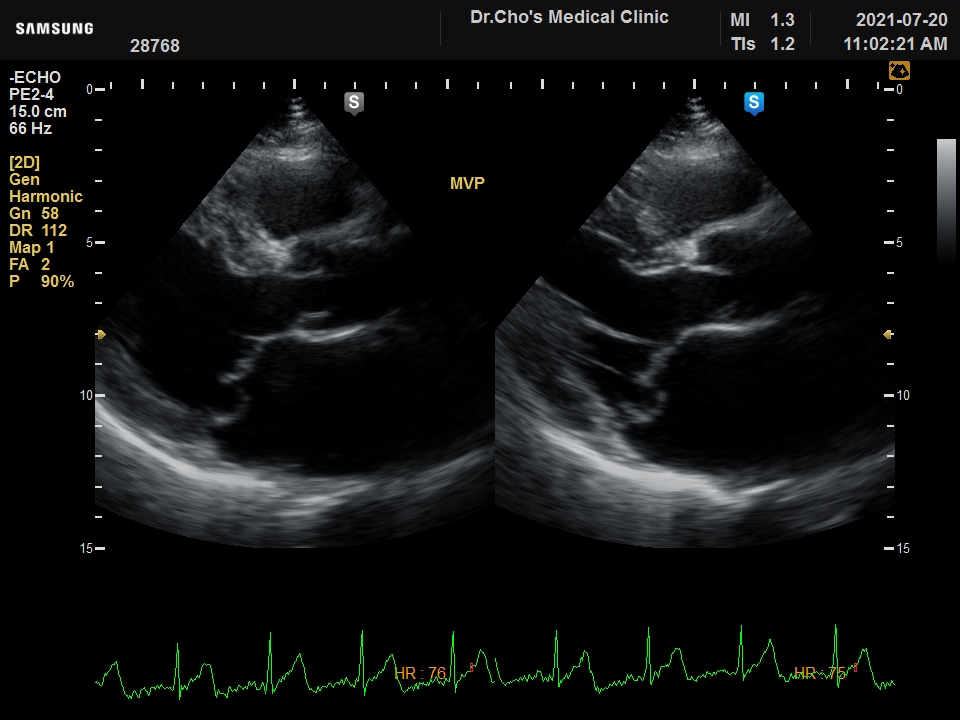

½Â¸ðÆÇ Å»...